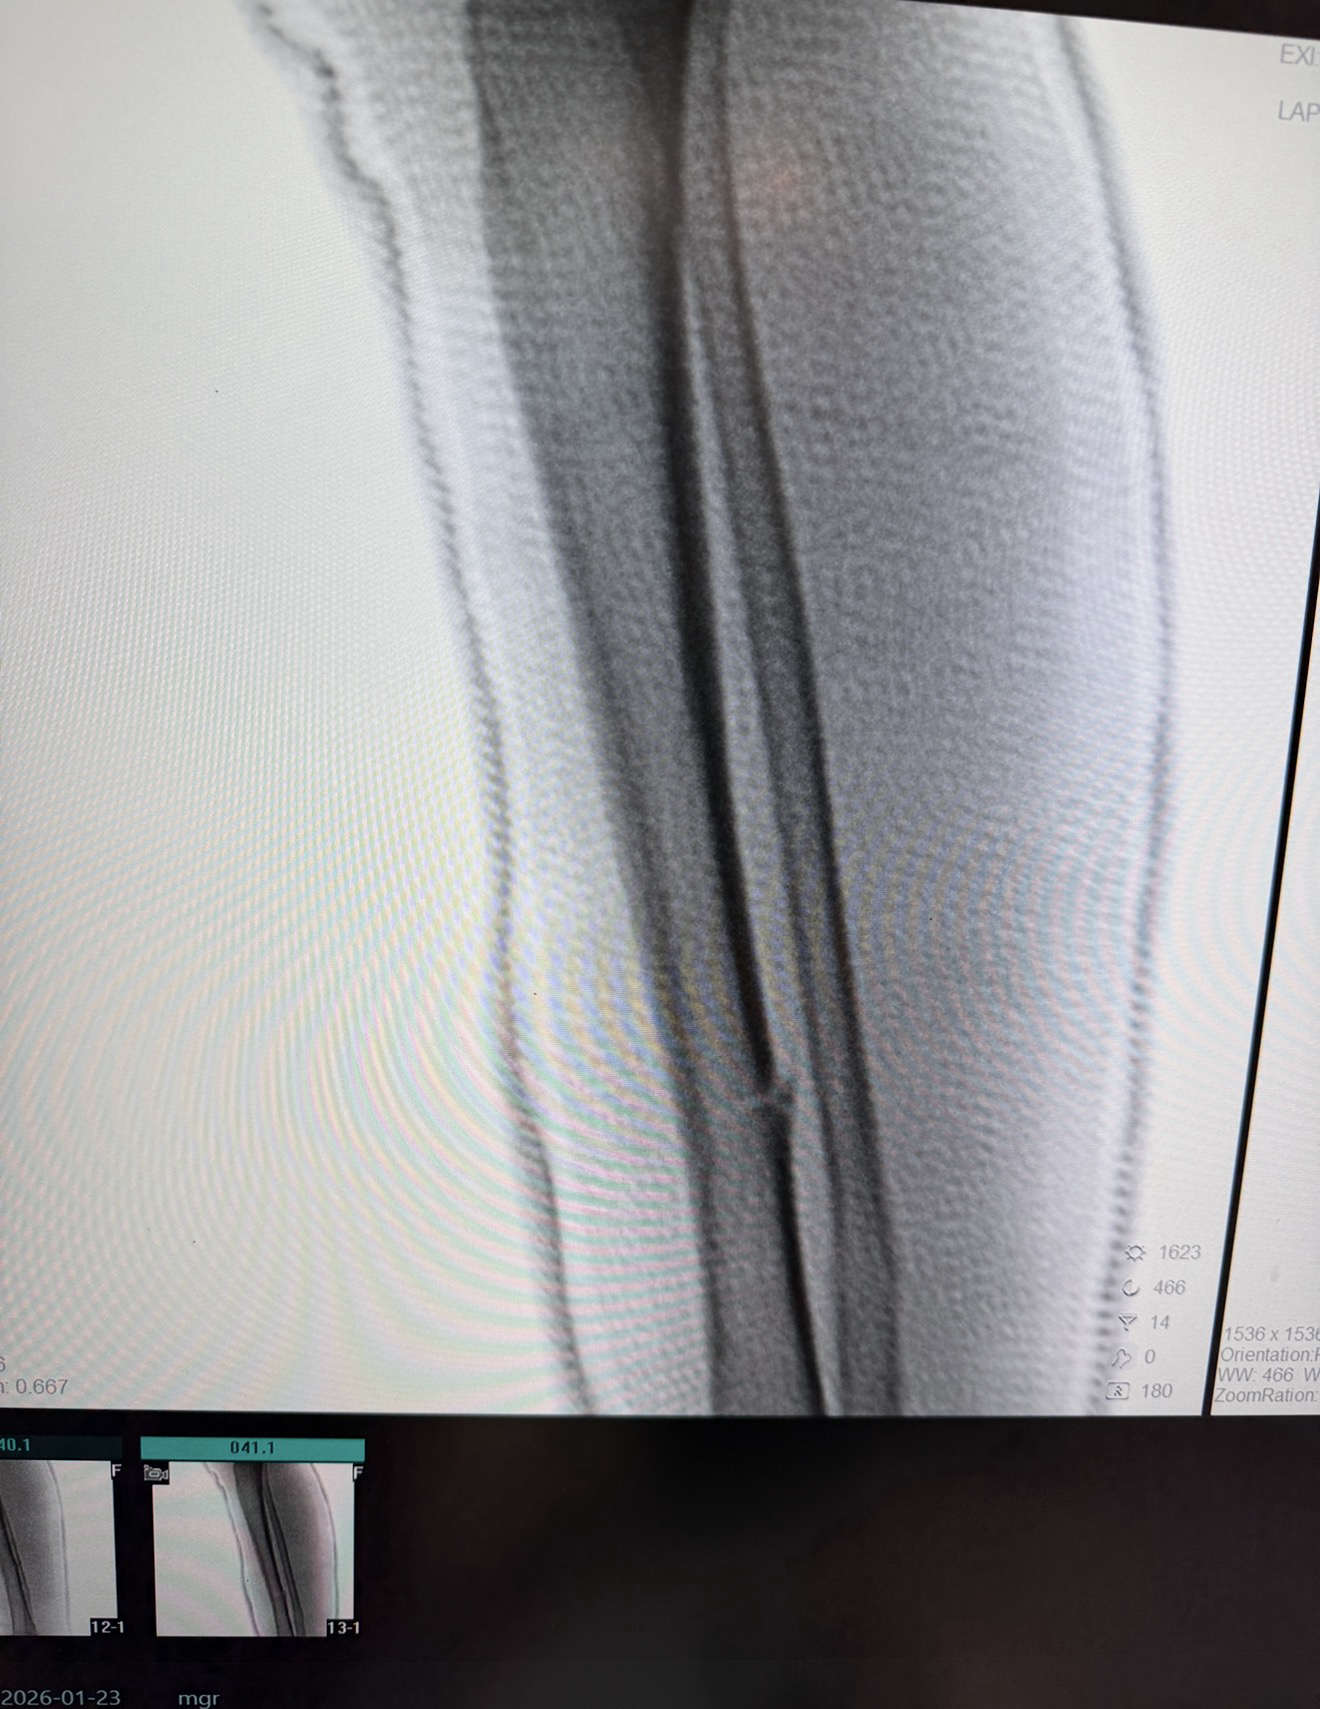

CLOSED REDUCTION AND ABOVE KNEE CAST OF 5 YEAR OLD CHILD